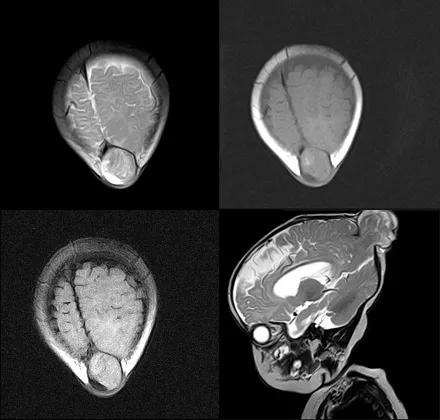

case 1:男,1 岁,生后不能抬头,不能独坐。

诊断:先天性巨脑回畸形及胼胝体发育不良